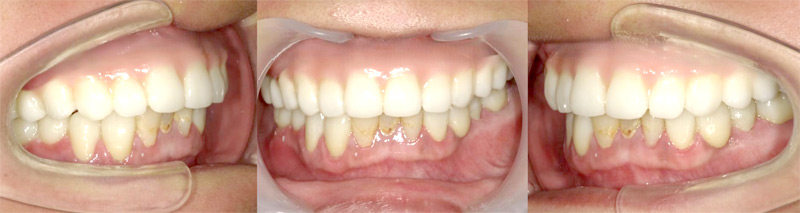

施行名 : 審美歯科(虫歯などをインプラント体によって改善する施術)

副作用やリスク : 麻酔で腫れやむくみを生じる場合があります。

また、劣化や口内の手入れを怠ることにより脱落する場合があります。

施術の価格:8万〜90万(税抜き)

※個人差があり、効果を保障するものではありません